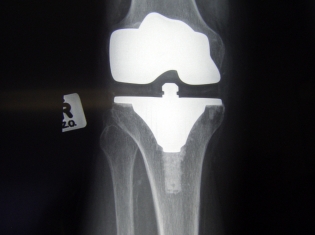

Total knee replacement is a largely successful surgery for the treatment of severe knee arthritis in older adults. While knee replacement surgery is an uncommon treatment for patients with JIA, it is sometimes used to relieve pain and improve mobility in these younger patients.

The study included 217 patients who had undergone a total of 335 knee replacements, or total knee arthroplasty. Participants were treated at five hospitals between 1979 and 2011.

Results showed that the 10-year knee implant survival rate among JIA patients was 92.2 percent. The 20-year implant survival rate was 75.5 percent.

"While the implants lasted at least 10 years in 92 percent of JIA patients, the data show total knee replacements last slightly longer in elderly patients with osteoarthritis," Dr. Figgie noted.